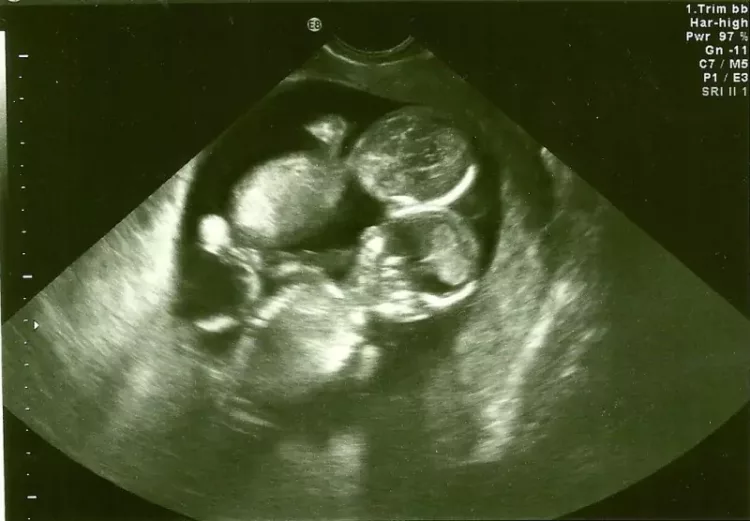

Când a sosit momentul primei ecografii, femeia a fost copleșită de sentimente materne și de o fericire absolută, iar medicul, cu care se cunoștea de mulți ani chiar a glumit: ,,Poate ai iar gemeni?” În cele din urmă se pare că gluma a devenit realitate, însă, din păcate, noutatea nu a fost sigură din prima zi, embrionii s-au separat abia după 8-13 zile de la fecundație, de aceea, între ei nu exista o membrană separatoare iar peste câteva zile copiii puteau deveni gemeni siamezi. Se pare că în sarcinile monocoriale exista riscul ca cordonul ombilical al unui făt să se înfășoare în jurul celuilalt, sufocându-l, tocmai de aceea gemenii au minime șanse de supraviețuire.

Medicul a sfătuit-o pe mamă să nu se îngrijoreze și să lase totul în mâinile naturii. După a 28-a săptămână de sarcină, mămica a stat 35 de zile în spital, totul pentru ca cei doi micuți să aibă șanse de supraviețuire. În cele din urmă a născut prin cezarină, iar când medicii au văzut cordoanele ombilicale, în sala de operații s-a lăsat o liniște de mormânt.

Cordoanele ombilicale erau înodate, arătau exact ca o împletitură și e foarte greu de crezut că fetițele au putut supraviețui în astfel de condiții. Dar mai existau și alte probleme. Gemenele s-au născut prematur, și, deși șansele erau foarte mici, ele erau perfect sănătoase. În cazul în care mai așteptau câteva ore, ele nu ar fi trăit.